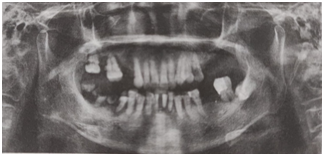

女,72歲。要求行上下頜活動(dòng)義齒修復(fù)。檢查:右上56、左上67、左下6缺失:右上7、右下5、左下12松動(dòng)Ⅲ度;右上8遠(yuǎn)中鄰面齲,不松動(dòng),叩痛(-);左上5近中齲壞,不松動(dòng),叩痛(+);左下7(牙合)面及近中可見大面積金屬充填物,探及繼發(fā)齲,叩痛(-),不松動(dòng),伸長(zhǎng)明顯;右下12松動(dòng)I~Ⅱ度;右下4伸長(zhǎng),松動(dòng)Ⅰ度;右下67殘根;口腔衛(wèi)生差,余留牙可見大量牙石,牙齦紅腫。曲面斷層片如圖所示。在上下頜行活動(dòng)義齒修復(fù)前準(zhǔn)備工作正確的是

【答案解析】修復(fù)前準(zhǔn)備包括拔除殘根,拔除Ⅲ度松動(dòng)牙,松動(dòng)I~Ⅱ度牙齒不應(yīng)拔除,故A項(xiàng)錯(cuò)誤;而對(duì)于左下8骨埋伏牙,不影響義齒修復(fù),不用拔除,所以選項(xiàng)B錯(cuò)誤;對(duì)于過度伸長(zhǎng)牙齒,根療后應(yīng)大量磨改并行人造冠修復(fù)調(diào)整(牙合)曲線,故選項(xiàng)C中依照原有高度行冠修復(fù)是錯(cuò)誤的;對(duì)于大面積缺損患牙應(yīng)行人造冠修復(fù),故D項(xiàng)中左上5牙根管治療后直接樹脂充填治療錯(cuò)誤;修復(fù)前牙周病患者需行牙周治療,此外,余留牙應(yīng)行咬合調(diào)整以改善平面,故E正確。